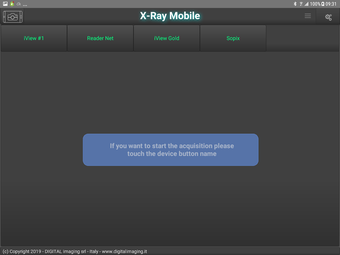

X-Ray Mobile is an Android app that allows users to acquire x-ray images directly on their mobile device. This app is especially useful for those in the medical field who need to take x-rays on the go. With X-Ray Mobile, users can also capture pictures from their camera and send them to a connected PC. The app uses WiFi to connect to the PC, making it easy to transfer images quickly and efficiently.

The interface of X-Ray Mobile is simple and easy to navigate. Users can easily switch between the camera and x-ray modes, making it easy to capture the images they need. The app also includes a number of settings that allow users to adjust the brightness and contrast of their images. Overall, X-Ray Mobile is a useful tool for anyone who needs to take x-rays on the go.